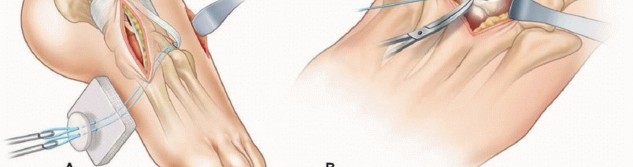

Anterior tibialis tendon transfer does not correct restricted subtalar motion.It is important to confirm that the ossific nucleus of the lateral cuneiform is present in order to place the anterior tibialis tendon into an appropriate anchor site. ## Positioning The patient is placed in the supine position on a standard operating table or the legs draped over a hand table.Either positioning is done in a way to ensure good fluoroscopic images.A well-padded, thigh-high tourniquet should be placed before preparing and draping the patient. ## Approach A medial incision is based over the insertion of the anterior tibialis tendon.From this incision, the surgeon may be able to perform an opening wedge osteotomy of the medial cuneiform if indicated.Once the anterior tibialis tendon is detached, a lateral incision is based over the lateral cuneiform. Fluoroscopic imaging can assist in planning this incision.The lateral incision may need to be longer and more laterally based should the surgeon decide to perform a cuboid closing wedge osteotomy at the same time. ## TECHNIQUES 1. ## Full Anterior Tibialis Tendon Transfer to the Lateral Cuneiform 5, 11 ### Approach A 4-cm long dorsal-medial longitudinal skin incision is made over the course of the anterior tibialis tendon from the inferior margin of the ankle retinaculum (the superior limb of the inferior extensor retinaculum) to its palpable distal insertion based over the medial cuneiform ( TECH FIG 1).Dissection is carried down through subcutaneous tissues and the inferior limb of the inferior extensorretinaculum to expose the tendon sheath.The anterior tibialis tendon sheath is incised sharply and opened as far distally as possible and then proximally to just short of the ankle retinaculum.A hemostat is placed under the anterior tibialis tendon to help expose the insertion.This broad extensive insertion is detached as far distally as possible to gain maximum length of tendon for the transfer.It is critical to obtain as much length as possible. Illustration 10 for Why Anterior Tibialis Muscle Transfer Fixes Clubfoot --- Illustration 11 for Why Anterior Tibialis Muscle Transfer Fixes Clubfoot ### TECH FIG 1 • A. Two incisions are made. B. The medial incision is made over the course of the tibialis anterior tendon. The surgeon frees the tendon from its broad insertion as far distally as possible and proceeds proximally as far as the ankle retinaculum. * Transferring the Tendon Once the tendon is freed and detached distally, a strong absorbable suture (eg, 1-0 Vicryl) is woven in a Bunnell-type fashion through the anterior tibialis tendon.Care is taken to weave the suture in a fashion that does not lead to a bulbous end, thus making the tendon difficult to deliver to the lateral wound and subsequently pass into the lateral cuneiform.Occasionally, the loose ends of the tendon insertion are trimmed or incorporated with a 3-0 absorbable suture to facilitate passage and anchoring.By pulling on the suture, the tendon is gently pulled distally while the soft tissue attachments to the tendon are freed up to, but not beyond, the ankle retinaculum.To avoid bowstringing of the tendon, it is important not to release the ankle retinaculum. A dorsal-lateral longitudinal incision, 1.5 to 2 cm long, is made over the lateral cuneiform.The lateral cuneiform is identified just proximal to the base of the third metatarsal.

Dissection is carried down through subcutaneous tissues to the toe extensors.To expose the lateral cuneiform, the toe extensors are retracted medially and the extensor digitorumbrevis muscle is retracted laterally.A cruciate periosteal incision is made directly over the lateral cuneiform, carefully avoiding the adjacent joint articulations.In young children, a Keith needle is used to fluoroscopically locate the center of the ossific nucleus.In older children, a small periosteal elevator is used to elevate the periosteal flaps off the lateral cuneiform.Occasionally, these flaps may be sutured into the transferred tendon, thus supplementing fixation. In young children, however, it may be difficult and futile to elevate perichondrium from the predominantly cartilaginous bone.A blunt hemostat is then passed from the lateral incision over the lateral cuneiform and under the extensor tendons to the point where the anterior tibialis tendon passes beneath the ankle retinaculum.Use the hemostat to develop a tract for the transfer of the anterior tibialis tendon.The hemostat is passed into this same tract into the medial wound to grasp the suture ends and bring the anterior tibialis tendon into the lateral wound ( TECH FIG 2).Ensure that the available length of the tendon will reach the proposed transfer site into the lateral cuneiform. ### Attaching the Transferred Tendon A drill bit is selected to be slightly larger than the diameter of the sutured anterior tibialis tendon end.Once the bit is selected, make a hole directly in the center of the lateral cuneiform, drilling just through the plantar aspect of the bone (dorsal to plantar while aiming for the arch of the foot).The suture ends of the tendon are threaded onto Keith needles ( TECH FIG 3A).While the foot is maximally dorsiflexed and everted, the suture needles are passed through the lateral cuneiform drill hole and out through the plantar aspect of the foot, guiding the tendon through the drill hole. Illustration 12 for Why Anterior Tibialis Muscle Transfer Fixes Clubfoot --- Illustration 13 for Why Anterior Tibialis Muscle Transfer Fixes Clubfoot ### TECH FIG 2 • The freed anterior tibialis tendon is brought into the lateral wound. The tendon is confirmed to easily and reproducibly slide into its new insertion.This is a critical step: Be certain that the tendon reliably enters the anchoring hole after the skin is closed when the foot is dorsiflexed and when the suture is tensioned. Smooth passage of the tendon into the third cuneiform may be facilitated by a drop or two of sterile mineral oil.The suture needles on the plantar aspect of the foot are passed through a nonadhesive dressing (eg, Adaptic) and a sterile felt pad.At this time, it is advisable to irrigate and close all other associated wounds, leaving the lateral recipient wound for last.This way, the surgeon can ensure that the anterior tibialis is in the intended position just before dressing and cast application.The periosteum of the lateral cuneiform is sutured with two interrupted absorbable sutures to the transferred anterior tibialis tendon while it is pulled into the recipient site ( TECH FIG 3B).The lateral wound is irrigated and closed in layers while the foot is held in a dorsiflexed position, thus ensuring that the anterior tibialis remains in the hole and the continuity of the periosteal sutures is preserved.Sterile dressings are applied while an assistant simultaneously maintains the foot dorsiflexed with tension on the suture.The distal foot and ankle portion of a toe-to-groin cast is applied while ensuring that the suture ends of the tendon are in tension.In the past, we have tied the button over the felt underneath the cast. However, a high rate of pressuresores has led us to consider alternative fixation.After the cast is hardened, the suture is tied over a button on the exterior of the plantar aspect of the cast ( TECH FIG 3C).To prevent plantar pressure sores, make sure the plaster is sufficiently hardened. Commercially available suture anchors can also be used to facilitate fixation of the tendon.Some surgeons will perform the exact procedure except transfer the whole tendon into the cuboid. These surgeons choose this

insertion site if the foot has a concurrent fixed forefoot deformity and mild hindfoot varus that they choose not to correct. Illustration 14 for Why Anterior Tibialis Muscle Transfer Fixes Clubfoot --- Illustration 15 for Why Anterior Tibialis Muscle Transfer Fixes Clubfoot Illustration 16 for Why Anterior Tibialis Muscle Transfer Fixes Clubfoot ### TECH FIG 3 • A. The suture ends of the tibialis anterior tendon are threaded onto Keith needles and passed into the drill hole through the plantar aspect of the foot. The tendon is guided into the drill hole. B. While the foot is maximally dorsiflexed and everted, the tendon is secured. The periosteum of the third cuneiform is sutured with interrupted nonabsorbable sutures into the transferred tibialis anterior tendon. C. The cast is molded and hardened with the foot in dorsiflexion and eversion and with the suture ends under appropriate tension. The suture is tied over a button on the exterior of the hardened cast to prevent plantar pressure sores.We prefer to correct the fixed deformity and transfer the anterior tibialis into the lateral cuneiform, as we fear overcorrection from the more lateral insertion into the cuboid.Some surgeons add a third incision at the anterior distal tibia directly over the anterior tibialis tendon and just lateral to the tibial crest. The tendon can be easily palpated. The tendon sheath is incised here and the freed distal tendon end is pulled with a hemostat into this incision. From this incision, the freed distal tendon end is eventually pulled into the lateral incision for attachment. 1. ## Split Anterior Tibialis Tendon Transfer ### Approach A 4-cm long dorsal-medial skin incision is made over the course of the anterior tibialis tendon from the inferior margin of the ankle retinaculum (the superior limb of the inferior extensor retinaculum) to its palpable distal insertion based over the medial cuneiform.Dissection is carried down through subcutaneous tissues and the inferior limb of the inferior extensor retinaculum to expose the tendon sheath.The anterior tibialis tendon sheath is incised sharply and opened as far distally as possible and then proximally to just short of the ankle retinaculum.The lateral half of the anterior tibialis tendon insertion is detached as far distally as possible to gain maximum length of tendon for the transfer.A strong absorbable suture (eg, 1-0 Vicryl) is woven in a Bunnell-type fashion through the lateral half of the anterior tibialis tendon. ### Transferring the Tendon The suture is grasped and pulled, allowing the lateral tendon to be gently dissected proximally but not beyond the ankle retinaculum.To avoid bowstringing of the tendon, it is important not to release the ankle retinaculum.A dorsal-lateral longitudinal incision, 1.5 to 2 cm long, is made over the cuboid in line with the fourth metatarsal axis.

Dissection is carried down through subcutaneous tissues to the toe extensors. To expose the cuboid, the toe extensors are retracted medially.A cruciate periosteal incision is made directly over the cuboid, carefully avoiding the adjacent joint articulations.An appropriate drill hole is then made in the cuboid, drilling dorsal to plantar in line with the fourth metatarsal axis and through the plantar aspect of the bone.A blunt hemostat is then passed from the incision over the cuboid under the extensor tendons to the point where the split anterior tibialis tendon passes beneath the ankle retinaculum.Use the hemostat to develop a tract for the transfer of the anterior tibialis tendon.The hemostat is passed into this same tract into the medial wound to grasp the suture ends and bring the split anterior tibialis tendon into the lateral wound.The suture ends of the tendon are threaded onto Keith needles. ### Fixation of the Tendon to Bone While the foot is maximally dorsiflexed and everted, the suture needles are passed through the cuboid drill hole and out through the plantar aspect of the foot, guiding the tendon through the drill hole.The tendon is confirmed to easily and reproducibly slide into its new insertion.The suture needles are passed through a nonadhesive dressing (eg, Adaptic) and a sterile felt pad.The periosteum of the cuboid is sutured with two interrupted absorbable sutures to the transferred split anterior tibialis tendon.The wounds are irrigated and closed in layers.Sterile dressings are applied while ensuring that the felt pad is flush with the plantar skin and the suture ends of the tendon are at hand.Alternative fixation may include use of suture anchor into the cuboid or transfer of the lateral half of the tendon into half of the peroneus brevis tendon or the peroneus tertius tendon prior to its insertion into baseof the fifth metatarsal. 9With the standard technique described earlier, the most medial muscle fibers proximally are the ones attached to the laterally transferred split tendon, resulting in a proximal crossing over as the split tendon is laterally transferred.Fennell and Phillips 4 suggest releasing the proximal medial insertion on the cuneiform instead of the distal lateral insertion on the first metatarsal to avoid this proximal crossing over, allowing for a more direct line of pull of the muscle on the transferred tendon.PEARLS AND PITFALLS --- | Indications ▪ Anterior tibialis transfer will work only as long as there is no fixed contracture.Flexibility of the foot is the main condition for a successful surgical result because the surgical procedure is based on the dynamic muscle imbalance of the forefoot.Positioning ▪ Use of a tourniquet at 200-250 mm Hg will allow easier surgery.Tendon ▪ Too short a tendon can make transfer difficult, so the surgeon should obtain as harvest much length as possible.Tendon ▪ It may be difficult to locate the lateral cuneiform in small children. Therefore, fixation intraoperative fluoroscopy should be available. | 1. Bowstringing and weakness by inadvertently cutting the extensor retinaculum should be avoided. 2. The surgeon should attach a suture to the released tendon to allow ease of handling and passing. This will also keep the tendon from fraying as it exits the donor site. 3. An absorbable suture is used to hold the tendon as it usually dissolves and weakens by 6 weeks. 4. Alternative forms of fixation may be considered in older children with large bones, such as a suture anchor ( FIG 7). 5. Overcorrection can be avoided with insertion of the full tendon transfer along the third metatarsal axis. For the split tendon transfer, the optimal site for insertion toobtain maximal dorsiflexion in biomechanical studies is along the fourth metatarsal axis. 7Wound closure 1. All wounds are closed except the recipient site to be sure that the transferred tendon stays in the tunnel. Also, the foot is kept in maximum dorsiflexion during final wound closure and casting. A well-trained assistant is paramount.Cast management 1. Pressure sores on the bottom of the foot can result from too much tension on the button. Therefore, it should be placed on the exterior of the cast. 2. Swelling and pressure sores may result if extensive and lengthy procedures are done. In these cases, prophylactic dorsal splitting of the cast in the operating room is important. Illustration 17 for Why Anterior Tibialis Muscle Transfer Fixes Clubfoot --- Illustration 18 for Why Anterior Tibialis Muscle Transfer Fixes Clubfoot ### FIG 7 • Intraoperative photo of lateral (recipient) wound. Alternative forms of fixation may be considered in older children with large bones, such as a suture anchor.